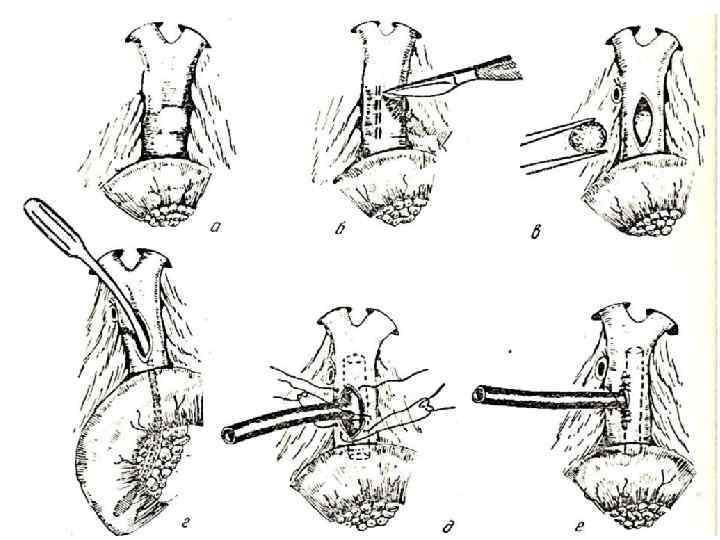

ХОЛЕДОХОТОМИЯ Көрсеткіштері: механикалық сарғаю, іріңді холангит, холедохолитиаз, бауырдан тыс өт жолдарының кеңеюі, үлкен бүртіктің стриктурасы.